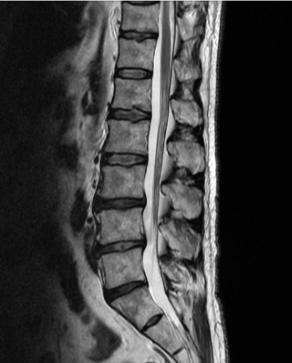

허리디스크는 디스크가 터져서 신경을 누를 경우 생기는 것으로 보통 4,5번에서 많이 발생하고 디스크가 터진 양이 적다면 터진 순간부터 수분이 날아가면서 양이 많이 없어지는데 그렇지 않고 양이 많을 경우 극심한 통증이 생깁니다.

허리디스크를 정확하게 진단하기 위해서는 엑스레이로는 힘들며, MRI를 통해 검사해야 정확하게 볼 수 있습니다.

MRI가 몸에 좋지 않지만 허리 통증으로 엑스레이만 진행 할 경우 오진이 많아 지속적인 통증이 계속 된다면 허리디스크를 의심하고 MRI 검사를 한번 받아보시길 권유드립니다.